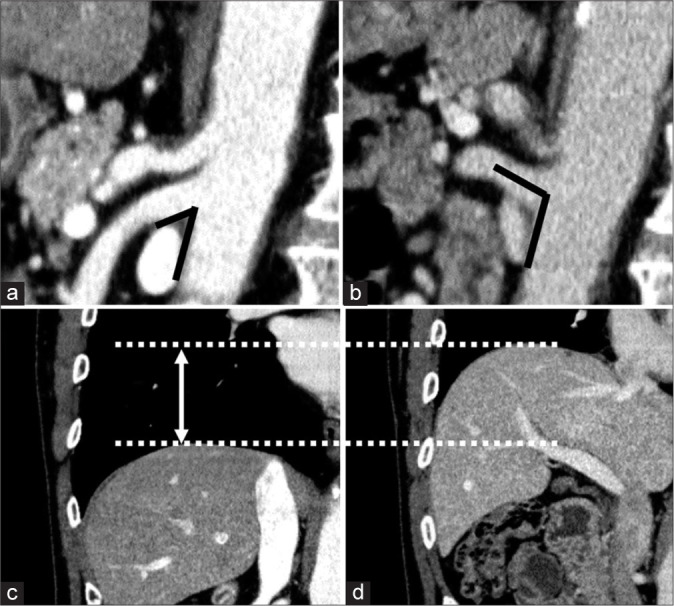

Material and methods: Sagittal reconstructed computed tomography (CT) images of 59 patients who underwent contrast-enhanced CT at end-inspiration and end-expiration between 2015 and 2020 were reviewed. All these patients underwent dynamic contrast CT during both inspiration and expiration for adrenal venous sampling purposes. Two experienced radiologists measured the aortomesenteric angle during both end-inspiration and end-expiration, and its variation rate. Pearson's or Spearman's correlation analysis was used to assess correlations between the angle or variation rate and height, weight, body mass index (BMI), visceral fat, subcutaneous fat, and diaphragm motion.

Results: The aortomesenteric angle was significantly larger at end-expiration (88.65 ± 25.15, 95% confidence interval [CI] 82.09-95.20) compared to end-inspiration (62.22 ± 21.90, 95% CI 56.51-67.93, P < 0.001). The aortomesenteric angles at both end-inspiration and end-expiration correlated significantly with weight, BMI, visceral fat, and subcutaneous fat. The strongest correlation was between aortomesenteric angle and visceral fat at both end-inspiration (r = 0.523, P < 0.001) and end-expiration (r = 0.546, P < 0.001). The variation rate correlated only with diaphragm motion (r = 0.550, P < 0.001).

Conclusion: The aortomesenteric angle at end-expiration was significantly larger than at end-inspiration, with the strongest correlation found between the angle and visceral fat.